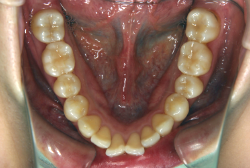

叢生(そうせい)

凸凹な歯並びのことを叢生といいます。矯正歯科に来院する患者様の主訴の中で、最も多いのが「配列の凸凹を真っ直ぐにしたい」というものです。歯の大きさと顎の大きさの調和がとれていないことが原因です。

凸凹を主体としたケースの場合、当院の平均治療期間は18ヶ月ですので、このケースは少し長めに経過しました。理由の一つは凸凹の程度がかなり重症だったと言うことですが、もう一つは、右下第2大臼歯が45度くらい前傾していたため、それを整直化させるために時間を要したと考えています。いずれにしても最終結果は大変よい状態と思います。

治療前は並びが乱れて見た目が悪いというのはもちろん問題ですが、歯科医学的に一番困るのは噛み合わせが悪いという点です。上下の犬歯(3番目の歯)は、上下的に離れた位置にあるため接触することができません。つまり歯としては存在していても、歯としては機能していないということです。